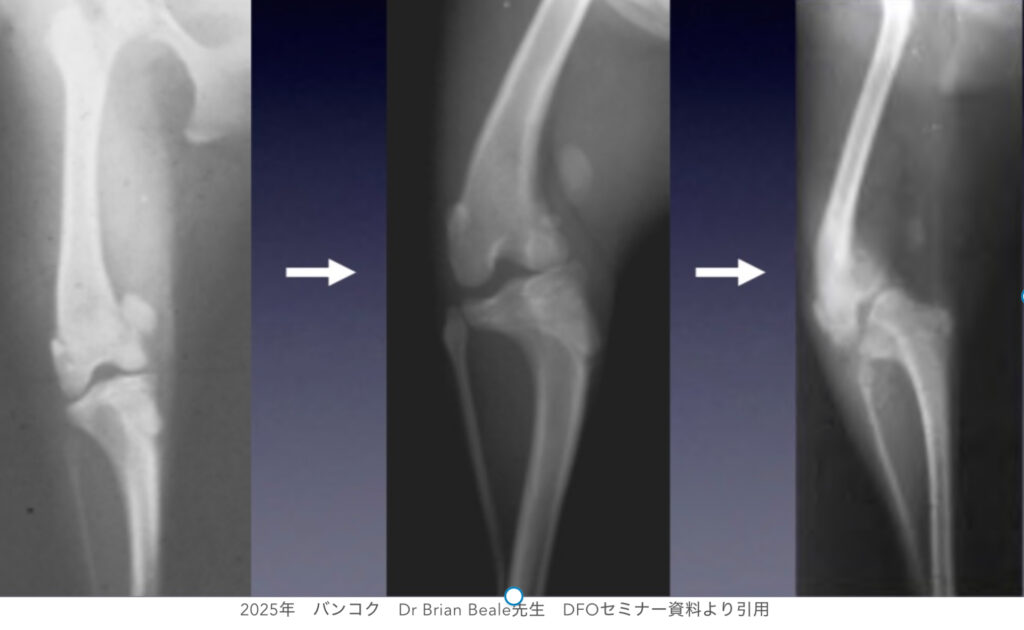

実際のパテラ症例の無治療経過観察の推移を示したレントゲン写真です。左側から時系列に並んでいますが、軽症であったパテラが、年数の経過とともに骨の変形が進み重症化していく様子がよくわかります。